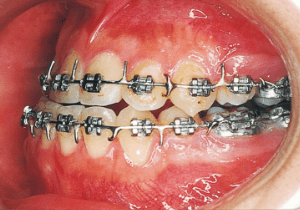

The Edgewise appliance was applied locally (8) and removed after 11 months (9). However, as the maxillary molar region gradually became crossbite, the maxillary arch was laterally expanded using a quad helix.

X-rays confirmed significant differences in the length and orientation of the mandibular ramus on the left and right sides. It was determined that orthodontic treatment alone would be insufficient, and a decision was made to proceed with treatment incorporating surgical intervention.

Although early treatment improved the slight deviation observed during the deciduous dentition stage, it became apparent that the deviation increased with age, eventually exceeding the limits of treatment. This appears to be an innate deviation, and the developmental pattern observed in this case seems to disregard the occlusion. Four first premolars were extracted (15), crowding was corrected and space closure was performed (16), and surgical intervention improved the deviation (17).